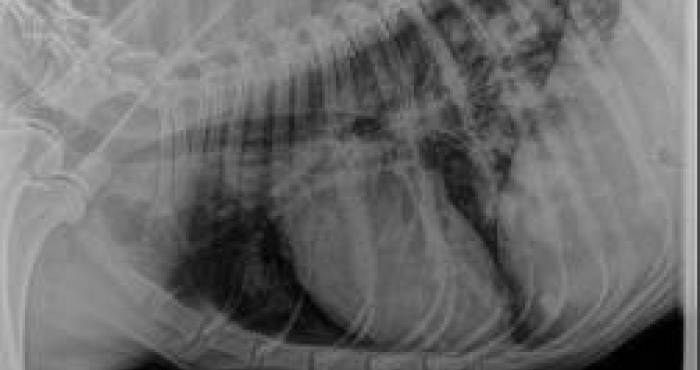

Imagens de cão boxer magro com ascite, com cardiomiopatia dilatada.